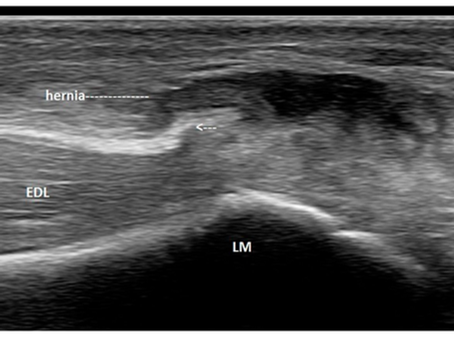

When “Ankle Sprain” Isn’t a Sprain: A Hidden Extensor Digitorum Longus Tear

A 25-year-old soccer player presented with ankle pain after an inversion injury. High-resolution ultrasound revealed a rare partial tear of the extensor digitorum longus with fascial rupture and myofascial herniation—findings missed on MRI. Dynamic scanning was key to diagnosis.